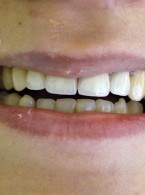

Dekoronacja

jako postępowanie zalecane w leczeniu pacjentów z postępującą pourazową infrapozycją zębów siecznych szczęki